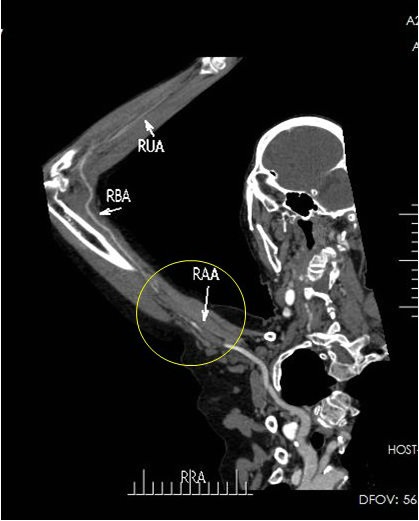

▲ 图4:CTA提示左侧腋动脉及肱动脉栓塞